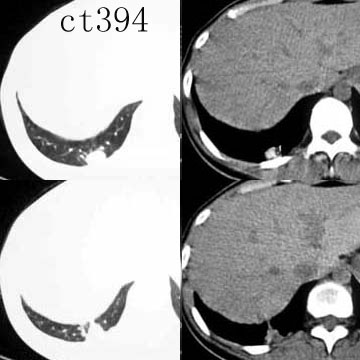

球形肺炎是大叶性肺炎的一种特殊表现[1],以肺的渗出实变为主。它的机理未明,可能是由于抗生素的广泛应用,大叶性或节段性肺炎发展受到限制而形成球形,其形成又与病缘菌的毒性数量及机体的免疫能力有关。病人多有感然症状,某些病人无明显感然症状。病变呈球形或椭圆形,大小不等,病灶密度多均匀,ct值稍低于软组织密度;或中央密度高,边缘密度低,显示晕圈状改变;有时可见空洞[2]。病灶边缘比较规则,也可不规则,有毛刺或呈锯齿状改变,但较模糊。位于肺周区,贴近胸膜,部分病栽表现为两侧缘垂直于胸膜,呈刀切样平直边缘。病灶周围血管纹理增多、增粗、常有局限性胸膜增厚。球形肺炎抗炎两周后,病灶即有缩小,最后能完全吸收。